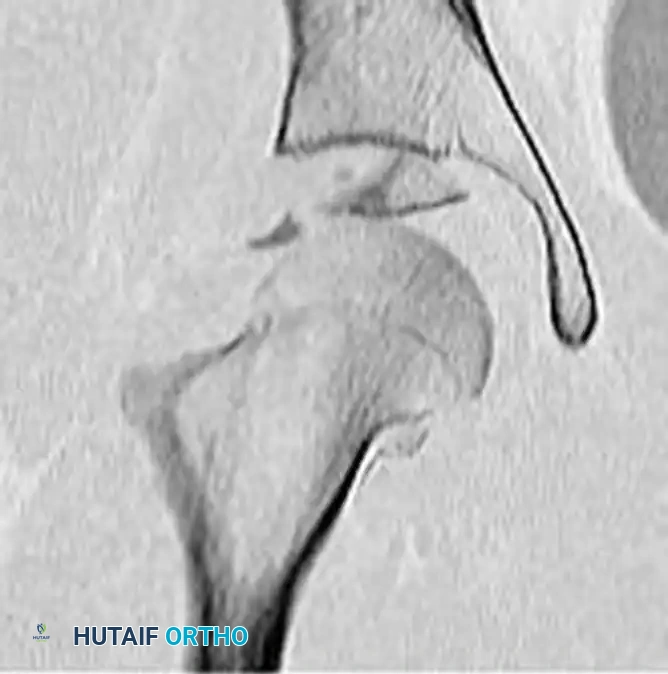

If the patient is hemodynamically stable and already in the CT scanner for a trauma pan-scan, pre-reduction axial and coronal CT images can provide invaluable information regarding intra-articular fragments and acetabular wall integrity.

FIGURE 55-52 D: Preoperative axial CT scan detailing the posterior displacement.